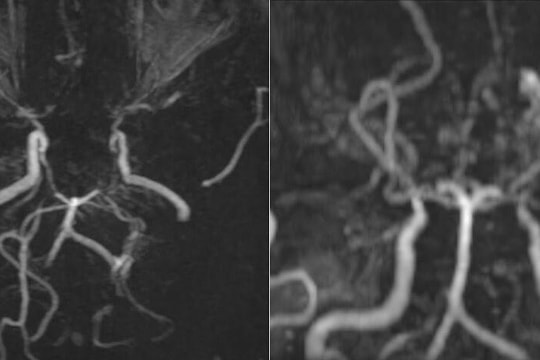

Mạch máu li ti như 'khói thuốc' trong não thiếu nữ

26/09/2025 17:37

Thiếu nữ 17 tuổi đau đầu, bác sĩ chẩn đoán mắc Moyamoya, bệnh lý khiến hình ảnh mạch máu não nhìn như “làn khói thuốc lá”, nguy cơ đột quỵ.

Mạch máu li ti như 'làn khói' trong não thúc đẩy đột quỵ

24/09/2025 08:00

Bệnh moyamoya gây ra những mạch máu nhỏ ti li như "làn khói", dễ vỡ và không đủ sức nuôi não, làm tăng nguy cơ đột quỵ.